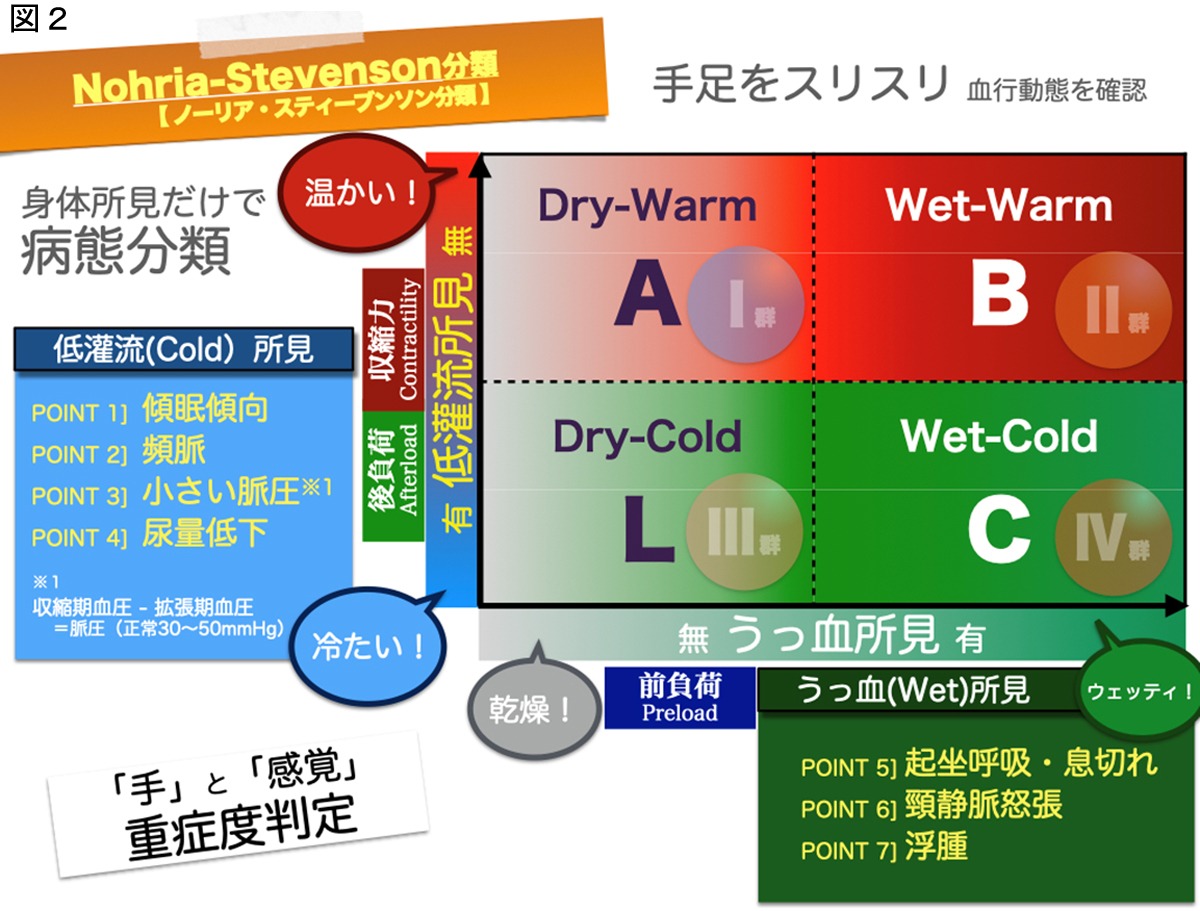

右心カテーテル検査では、心臓と肺を通って体内を循環する際の血行動態を評価します。心臓、肺、腎臓の合併症を検査するためによく使用されます。

この手順は、以下の評価にも使用されます。

IVと組み合わせて使用されることもあります。心臓の薬は点滴によって投与でき、この薬の効果はスワンガンツによって検査および監視できます。